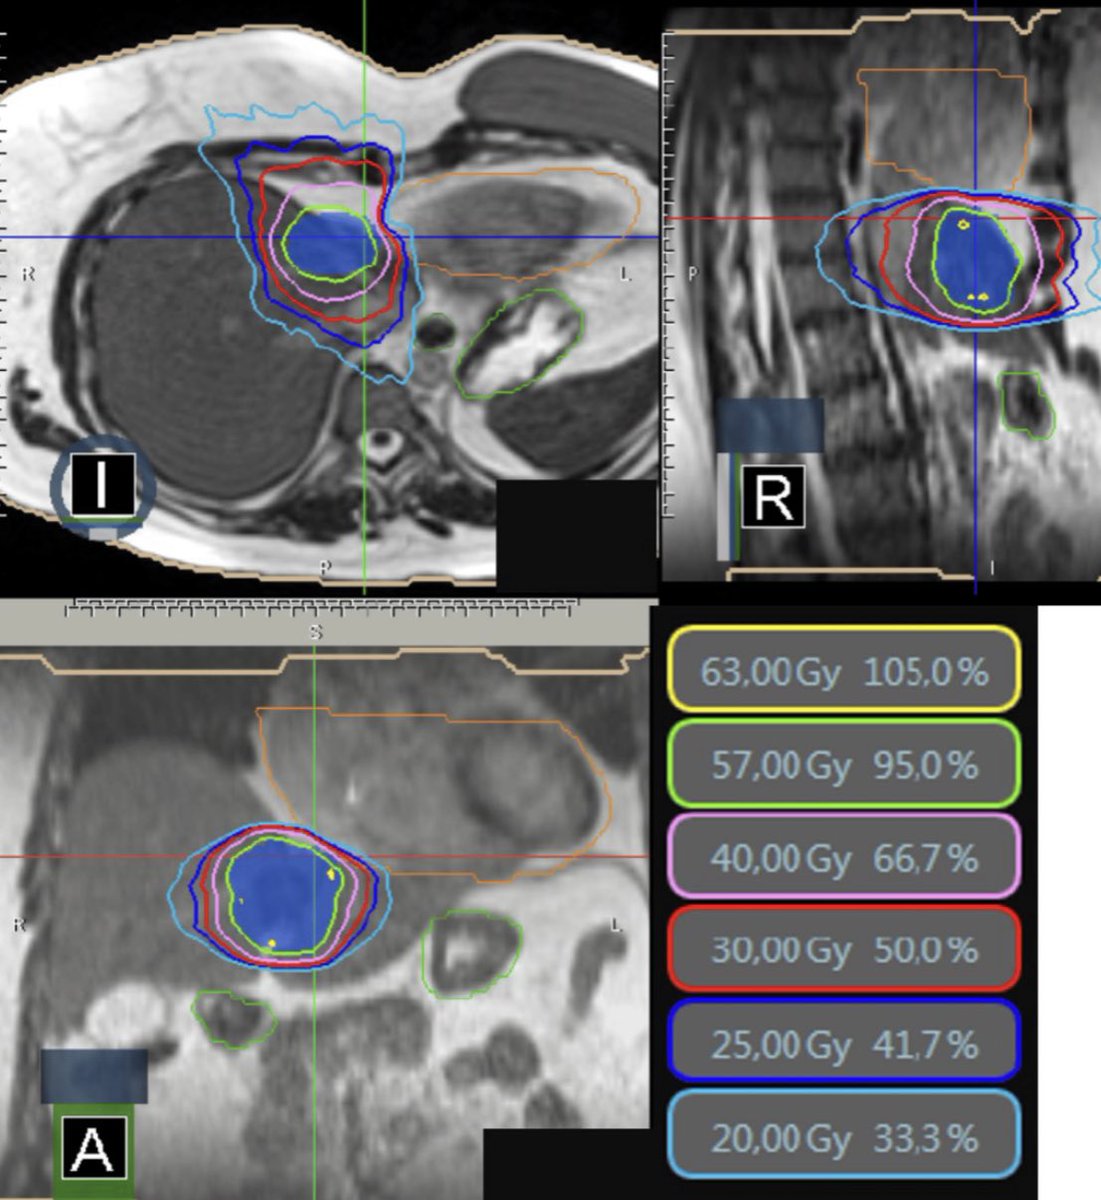

5️⃣ العلاج الإشعاعي المسلط بشكل مباشر الجسم (SBRT):

⬅️ باستخدامِ الطاقةِ من الأشعةِ السينيةِ أو البروتوناتِ، إذا لم تكُن الجراحة خيارًا مناسبا للمريض انا الصحه العامه او لتشعب الورم.